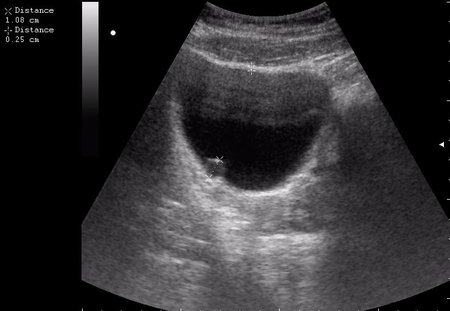

Сравните

Продольное сканирование мочевого пузыря После легкой перкуссии мочевого пузыря

ну... и сравнивать нечего, обычно так выглядят болота в Белоруссии, или первые 2 дня о.цистита